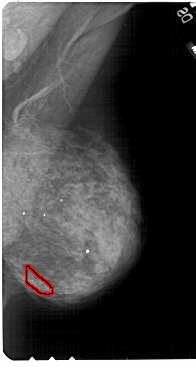

A_1810_1.LEFT_MLO

LEFT_MLO LINES 5491 PIXELS_PER_LINE 3256 BITS_PER_PIXEL 12 RESOLUTION 43.5 NON_OVERLAY

FILE: A_1810_1.RIGHT_MLO.OVERLAY

TOTAL_ABNORMALITIES 1

ABNORMALITY 1

LESION_TYPE CALCIFICATION TYPE PLEOMORPHIC DISTRIBUTION CLUSTERED

ASSESSMENT 4

SUBTLETY 2

PATHOLOGY BENIGN

TOTAL_OUTLINES 1

BOUNDARY